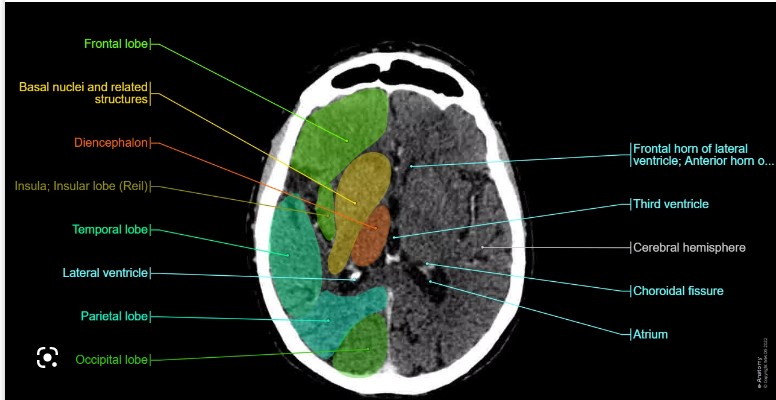

When reviewing a CT brain, systematically look for:

- Midline shift: Displacement of midline structures (falx cerebri, septum pellucidum) suggests mass effect from haemorrhage, tumour or major oedema.

- Haemorrhage: Hyperdense areas. Classify as epidural, subdural, intraparenchymal, or subarachnoid based on location and shape.

- Ischaemia: Hypodense regions in a vascular territory, loss of grey–white differentiation, sulcal effacement and early swelling.

- Ventricular size: Look for dilatation, compression or asymmetry suggesting hydrocephalus, raised ICP or mass effect.